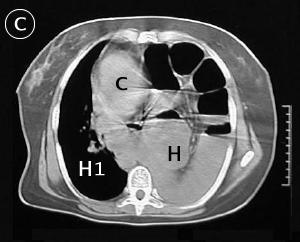

Corte Tomográfico C

c: corazón desplazado a la derecha.

H: El hemitorax izquierdo ocupado por las asas intestinales, ausencia de parenquima pulmonar

H1: Hemitorax derecho disminuido por el desplazamiento del mediastino.